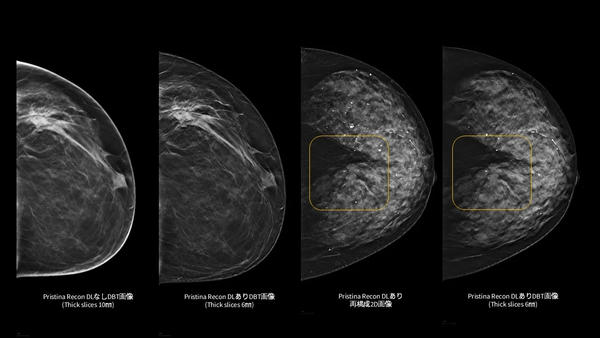

「Pristina Recon DL」は,ディープラーニングと逐次近似再構成技術を活用した,デジタルブレストトモシンセシス(DBT/3Dマンモグラフィ)向けの画像再構成技術。また,被ばく線量を増加させることなく,高画質で安定したDBT/3Dマンモグラフィ画像の提供を目指す。

さらに,ディープラーニングを用いた高度な画像再構成技術により,アーチファクト(虚像)や視覚的ノイズを低減し,微細構造の視認性を向上させる。これにより,DBT/3Dマンモグラフィおよび再構成2D画像の双方において,読影に必要な情報をより明確に可視化し,診断を支援する読影環境の向上に貢献する。